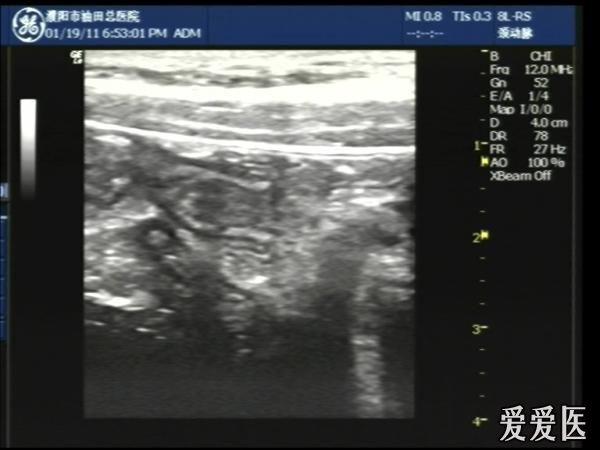

晚6点半,儿童、腹痛5日,无明显压痛及反跳痛。

超声检查:于下腹部可见“双环征象”,双环重叠长约6mm,检查期间观察可见肠蠕动;CDFI:未见明显异常血流信号。

超声提示:下腹部双环征,考虑肠套叠可能,请结合临床